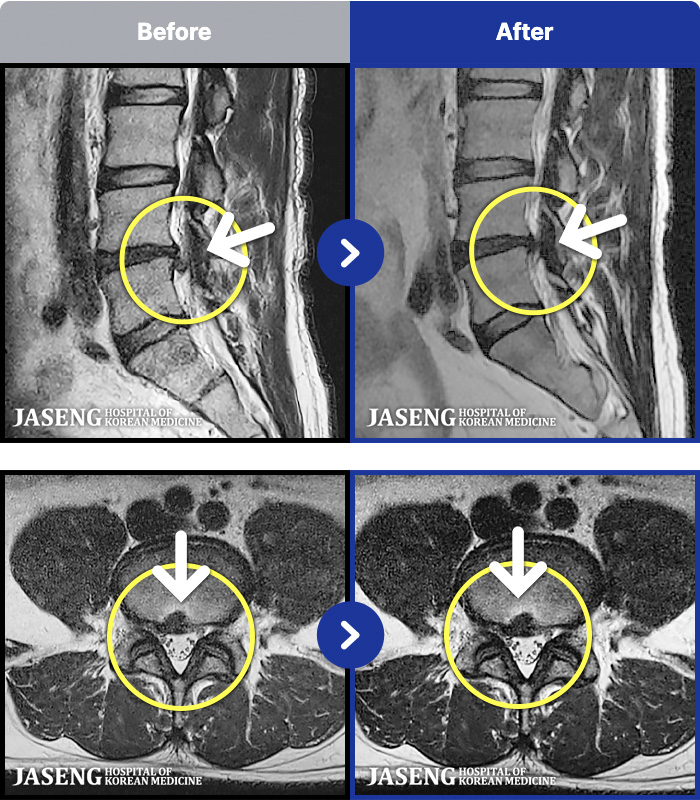

- MRI ġ

MRI ġ

1,240 MRI ũ ʸ Ȯϼ.